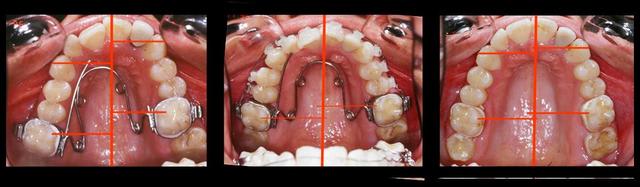

Voici un cas qui ressemble un peu a ton cas, en moins grave, mais qui peut te donner une idee sur ce qu'il faut faire.

Bref, le systeme de MacAndrews peut etre utile dans ces cas. Un arc de base de stabilisation basic, jambe du cote de la deviation contre la laterale, le cote oppose est a distance pour permettre le mouvement des 4 incisives. Une boucle au milieu du pont lateral sert de stop pour le ressort active de la quantite de deplacement desiree avec 3 mm de plus et insere pendant la fabrication de l'arc de base. On laisse faire le systeme tout seul.

Abd - Eugenol

Abd ressort cyjkzt - Eugenol

Abd ressort 2 mg2ndd - Eugenol

Abd fin lv84yz - Eugenol